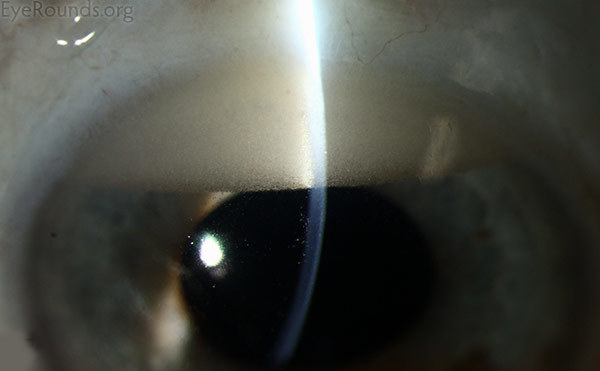

Hudson-Stähli Line

The Hudson-Stahli line is not associated with any pathology calling for clinical intervention. Formation of the line may depend upon the rate of tear secretion